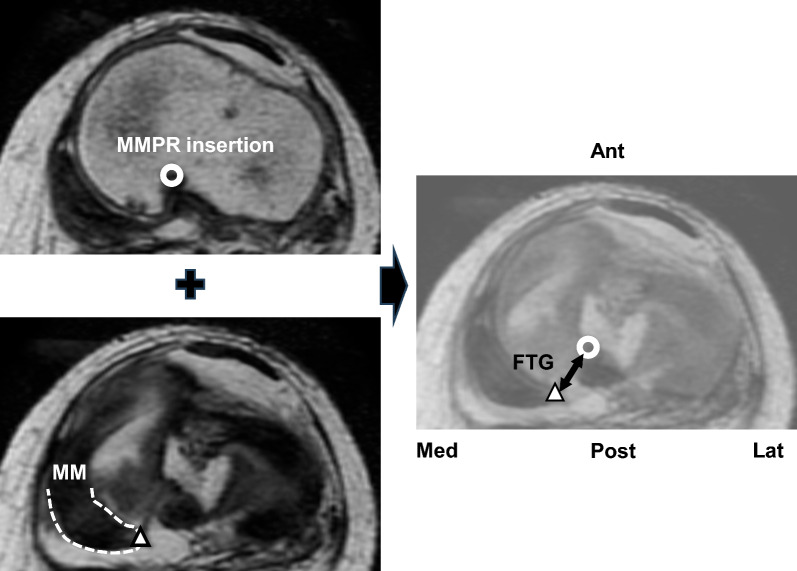

Methods: This retrospective observational study included 54 patients (mean age, 64.6 years; 13 males and 41 females) who underwent pullout repair for radial degenerative MMPR tear. Meniscus stability (scored 0-4 points) was assessed using a semi-quantitative arthroscopic scoring system during second-look arthroscopy 1 year postoperatively. The FTG was evaluated on preoperative axial MRI at 90° knee flexion. Other MRI measurements included MM extrusion (MME) at 10° knee flexion, MM posterior extrusion (MMPE) at 90° knee flexion, and MM posteromedial extrusion (MMpmE) at 90° knee flexion preoperatively and 1 year postoperatively. The correlation between the arthroscopic stability score and MRI findings was investigated. A receiver-operating characteristic curve was calculated to predict a good meniscus healing score (3-4 points). The correlation between the FTG and patient demographics, including time from injury to MRI, was analyzed.

Results: At 1 year postoperatively, MME increased by 1.1 mm, while MMpmE and MMPE decreased by 0.4 mm and 1.0 mm, respectively. The meniscus stability score was negatively correlated with the preoperative FTG (r = -0.61, p < 0.01). The time from injury to MRI was significantly correlated with the preoperative FTG. The receiver-operating characteristic curve identified an FTG cut-off value of 8.7 mm for predicting good postoperative stability, with sensitivity and specificity of 67% and 85%, respectively.